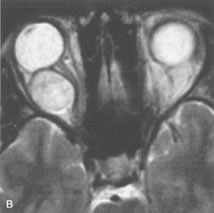

Breast carcinoma metastatic to the orbit has been demonstrated to be hypointense to the surrounding orbital fat on T1-weighted studies and hyperintense on T2-weighted images and has an affinity to the extraocular muscles (Fig. 20).50,64 The MRI characteristics of prostate carcinoma metastatic to the orbit have been described as involving the greater and lesser wing of the sphenoid, orbital roof, and optic canal. Diffuse bone hypertrophy with isointense or slightly hyperintense tissue on T1-weighted images represents the osteoblastic carcinomatous bone infiltration. Contrast enhancement is variable on T1-weighted and fat-suppressed images.65

Fig. 20. A. T1-weighted MR scan demonstrates nodular enlargement of both medial rectus muscles (arrows). B. T1-weighted fat-suppressed contrast-enhanced scan confirms the presence of small metnstatic deposits within the muscles (open arrows).